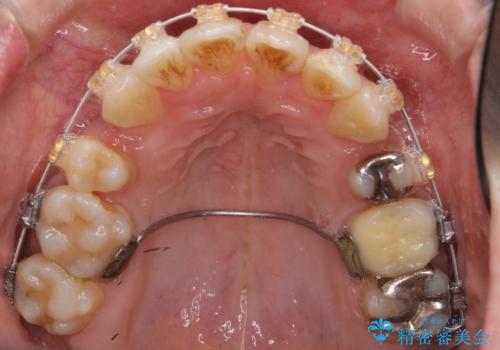

- 矯正装置

- 審美装置

- 治療計画

- 前歯のがたがた、出っ歯を主訴に来院。

がたつきは中等度で、上の前歯を下げるには歯を抜いてもスペースが不足していた為、上の奥歯を後ろに下げました。

下も混雑が激しく、歯を抜いてもスペースが不足していた為、下の前歯を少し削って小さくして並べています。

歯の移動量が大きく、また、少し歯も動きにくかったため矯正治療に時間はかかりましたがしっかり並べて前突感も大きく改善しました。